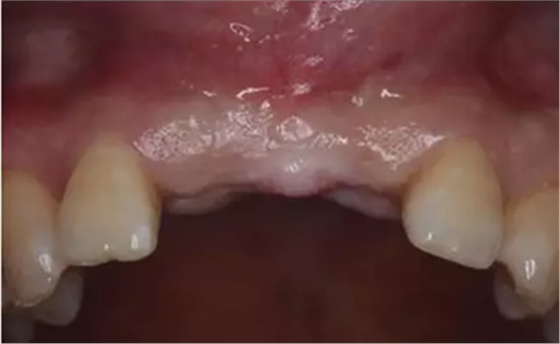

愈合基臺(tái)連接2周后

種植過(guò)渡義齒戴牙后1個(gè)月,患者希望改善義齒美觀度,并進(jìn)一步減少唇側(cè)凸度

患者試戴1個(gè)月后,發(fā)現(xiàn)牙齦塑性效果良好,過(guò)渡義齒穿齦部分不需要修改

種植過(guò)渡義齒戴牙后3個(gè)月,牙齦形態(tài)穩(wěn)定

過(guò)渡義齒制作完成及試戴

過(guò)渡義齒佩戴3個(gè)月后